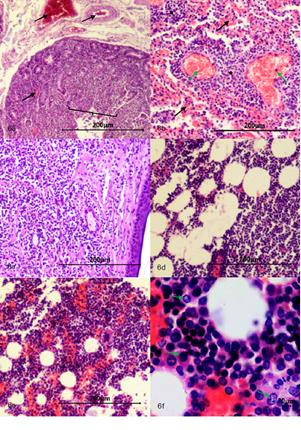

Intestino delgado. Se evidencia severos cambios microcirculatorios, múltiples focos de congestión, hemorragia y enlodamiento con distribución multifocal en mucosa, submucosa, muscular. La luz con gran cantidad de detritos celulares, se evidencia focos con modera atrofia y fusión de las vellosidades, focos con cambios asociados a muerte celular en la punta de la vellosidad y escasos focos de hiperplasia del epitelio que recubre la mucosa, núcleos con picnosis, cariorrexis y cariolisis, moderado infiltrado inflamatorio linfoplasmocitario con distribución difusa, severo edema de la submucosa (Figura 6a).

Pulmones. Severos cambios microcirculatorios y múltiples y extensas áreas de congestión, hemorragia, enlodamiento y edema con distribución difusa, presencia de múltiples focos correspondientes a células neoplásicas de origen linfoide; adicionalmente en epitelio bronquiolar se evidencian focos con cambios asociados a muerte celular, áreas de moderada hiperplasia del mismo, moderada hiperplasia de células caliciformes, focos de aplanamiento del epitelio bronquiolar y severo infiltrado inflamatorio predominantemente mononuclear compuesto por macrófagos, células plasmáticas y escasos PMNs neutrófilos con distribución bronquiointersticial (Figura 6b).

Piel. Epidermis aparentemente normal, en la dermis se evidencia proliferación celular neoplásica de células origen linfoide la cual se organiza a manera de paquetes celulares densos y en algunos áreas se organizan en forma de cordones pobremente delimitados por estroma de tejido conectivo que compromete a dermis superficial, dermis profunda, y tejido subcutáneo y tejido muscular. Las células son de forma redondeada núcleos grandes muy escaso citoplasma con moderado pleomorfismo celular, moderada anisocitosis, y moderada megalocitosis. Se evidencia moderado pleomorfismo nuclear, moderada anisocariosis y severa megalocariosis. No se contabilizaron figuras mitóticas en diez campos al azar a 400X, adicionalmente se evidenció la presencia de células neoplásicas dentro de lumen de algunos vasos sanguíneos (Figura 6c).

Tejido adiposo. Presencia de extensas áreas correspondientes a proliferación de células neoplásicas de origen linfoide con características similares a las mencionadas en hígado y páncreas (Figura 6d).

Médula ósea. Se evidencia severo aumento de la fracción celular con presencia múltiples focos de células neoplásicas aparentemente de origen linfoide (Figuras 6e, 6f).